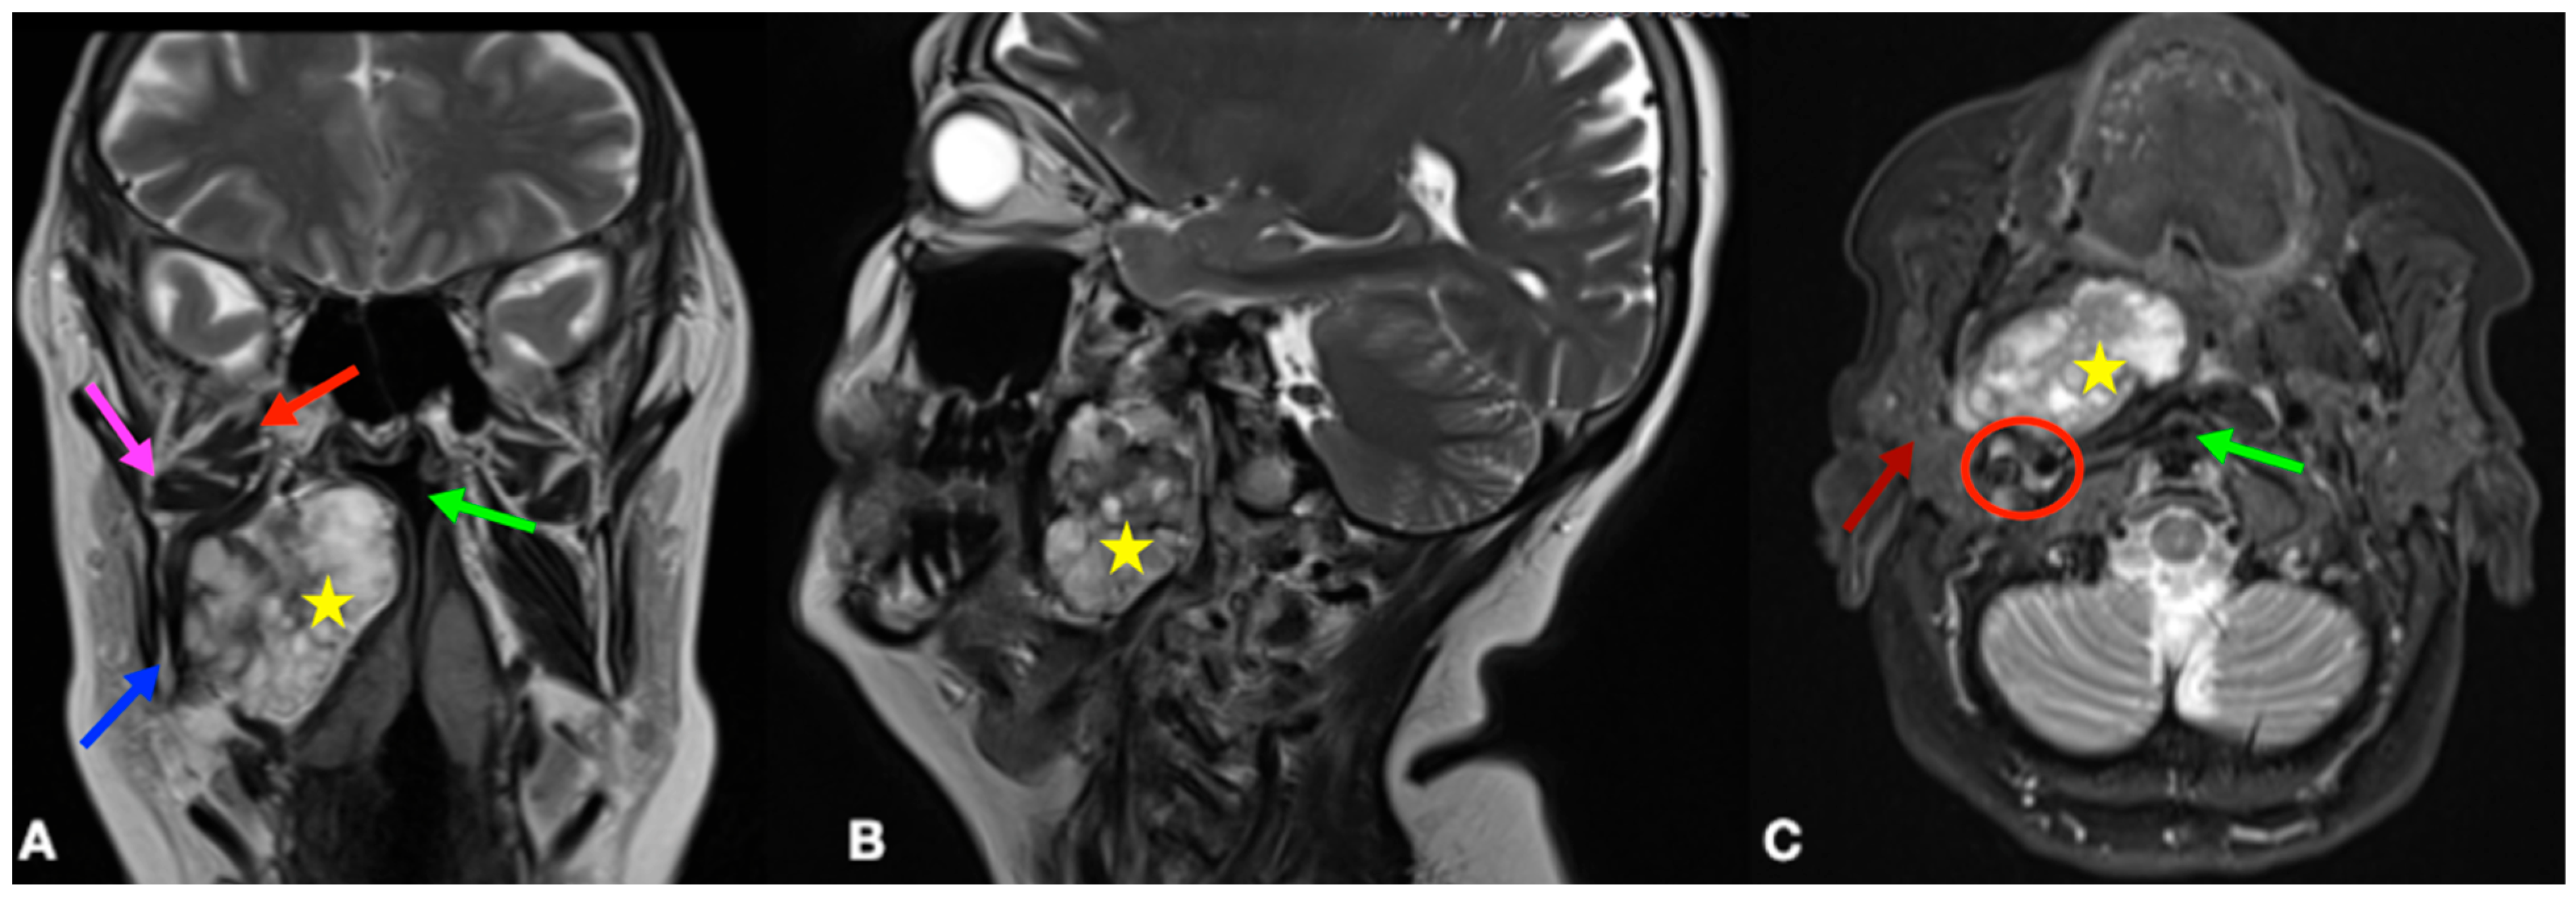

2. Case Presentation